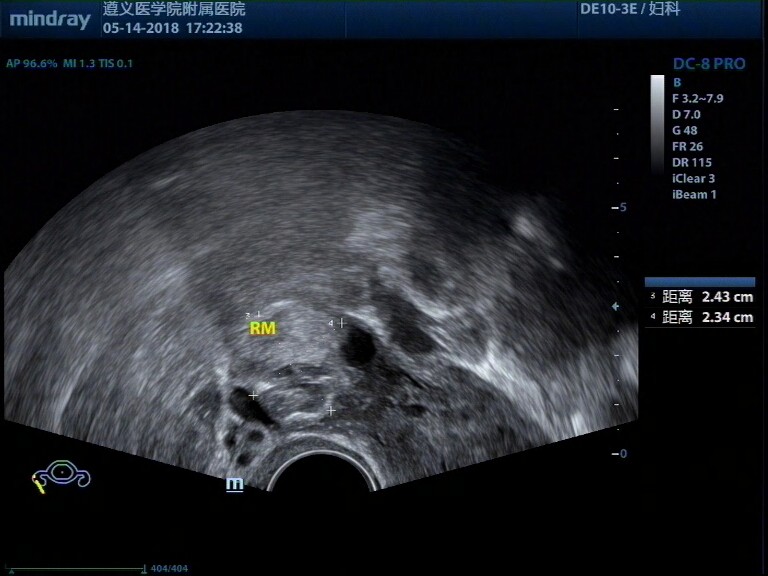

病例,31岁女性,纵膈子宫、畸胎瘤、子宫肌瘤

病例,31岁女性,纵膈子宫、畸胎瘤、子宫肌瘤。

病例来源遵义医学院附属医院